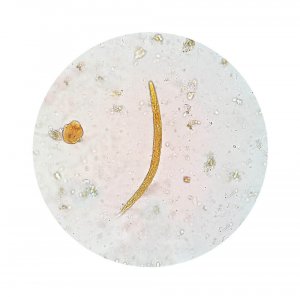

Справжня природа інфекції легко визначається за допомогою аналізу фекальних речовин. Це дозволить виявити, чи є активні амеби або кісти.

Специфічною причиною амебної дизентерії є мікроорганізм, який називається Дизентерійна амеба. Цей організм поширюється по всьому тілу через кал і передається іншим людям, коли він є в їжі або воді. Він вражає слизові оболонки кишківника, особливо товстого.